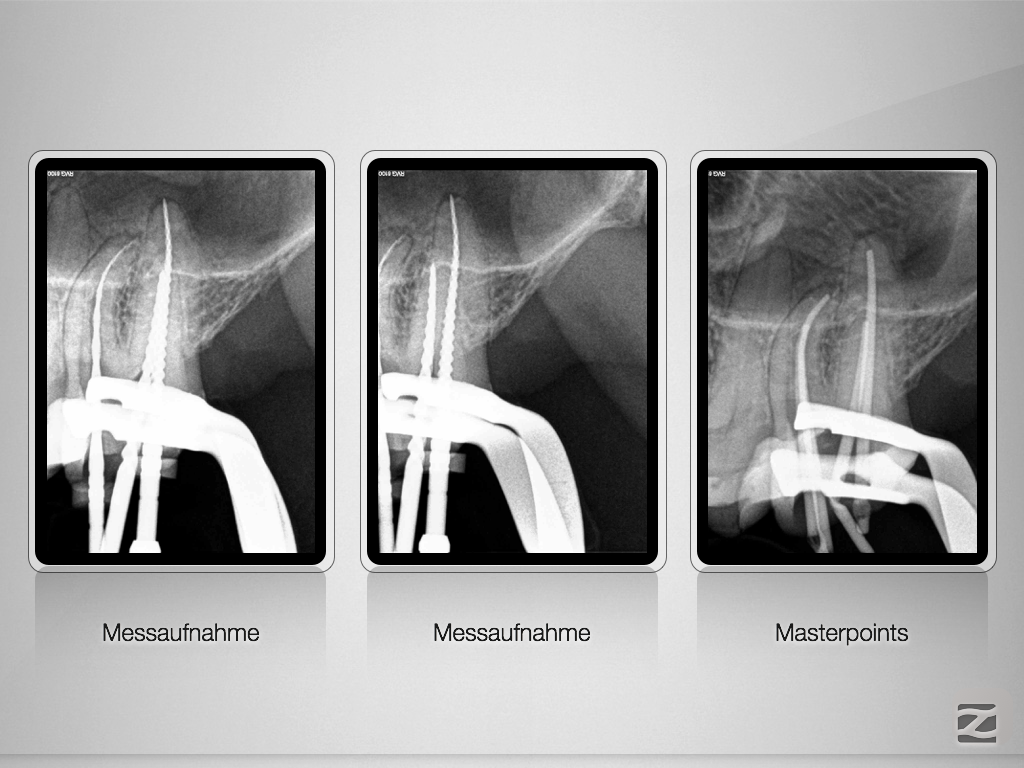

27D.007

Die gute alte Hedströmfeile